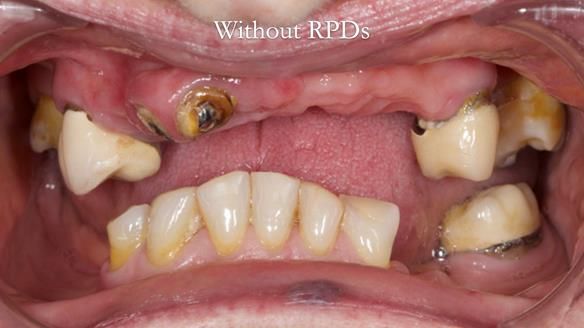

Aesthetically and functionally poor RPDs were replaced for Eileen, a 74 year old woman.

Referred to me by her general dental practitioner specifically for replacement RPDs.

- Missing teeth in the upper and lower jaws

- Upper and lower metal based RPDs, poorly fitting, worn occlusal surface, reverse curve aesthetics, lacking support

- Poor dental appearance with reverse incisal curve

- The upper right central and lateral incisors with post crowns. Healthy and functionally secure but with poor appearance, contributing to the reverse curve.

- Moderate to heavily restored dentition with deep overbite (Class 2 div II)

- Yellowish lower front teeth with small amount of wear.

- The lower right canine (LR3) is worn with MOD cavity.